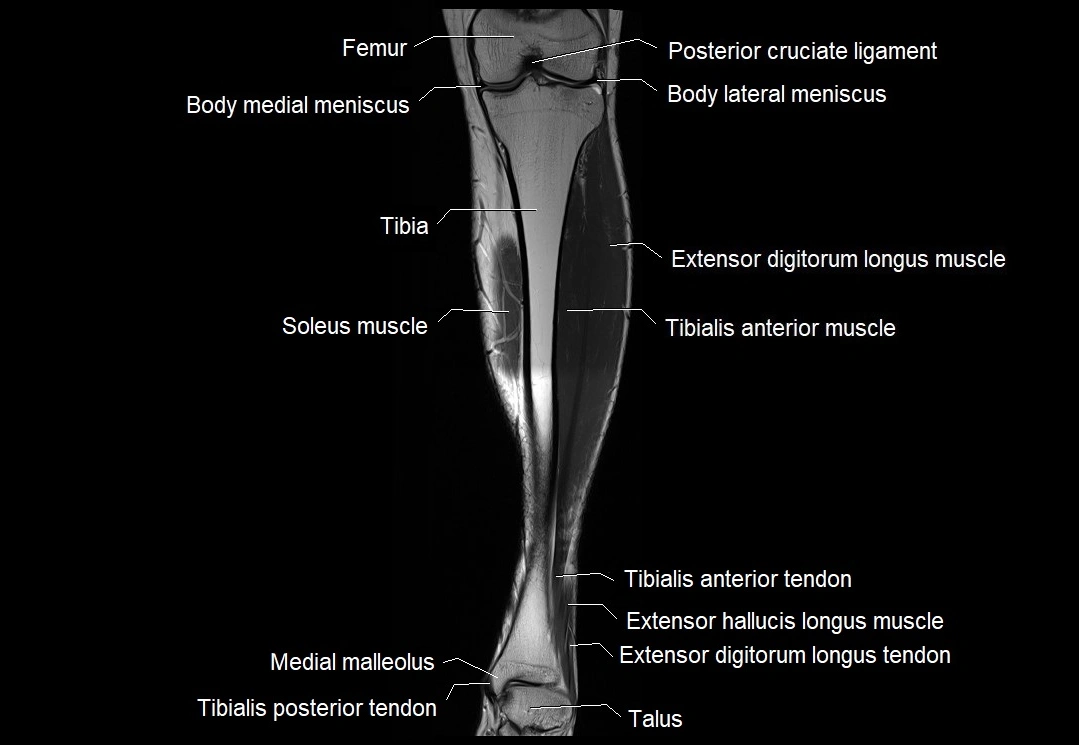

MRI image